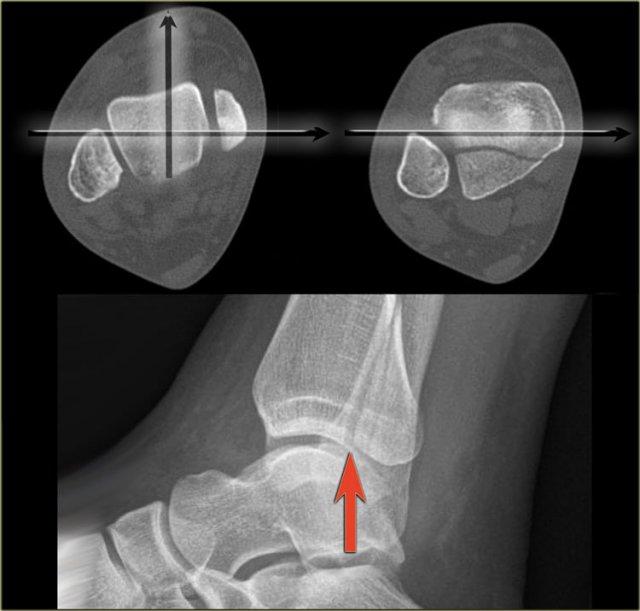

Định vị sai tư thế chụp nghiêng là lỗi phổ biến nhất trong chụp X-quang mắt cá chân bị chấn thương.

Vì bệnh nhân đang đau, kỹ thuật viên ngại để bệnh nhân xoay mắt cá chân hoàn toàn sang tư thế nghiêng.

Đây là một trong những lý do tại sao chúng ta bỏ sót rất nhiều gãy xương mắt cá sau.

CT cho thấy một gãy xương tertius lớn.

Trên phim chụp nghiêng và cả trên phim chụp thẳng AP và phim chụp Mortise, sẽ được trình bày trong phần về gãy xương tertius, gãy xương này không thể nhìn thấy được.

Giải thích là trên phim chụp X-quang nghiêng, xương mác chiếu vào giữa xương chày.

Chùm tia X không song song với đường gãy.

Vì đường gãy của gãy xương tertius luôn có hướng này, chúng ta phải nhấn mạnh tầm quan trọng của phim chụp nghiêng thực sự.

Trên hình chụp nghiêng được định vị tốt, gãy xương tertius hiện rõ ràng (mũi tên đỏ).

Đây là gãy xương duy nhất được phát hiện trên phim X-quang cổ chân, và bệnh nhân này được xác định có gãy xương Weber-C không ổn định và phải phẫu thuật.